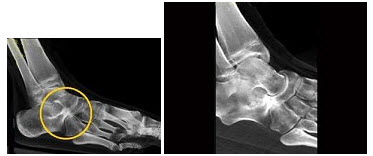

58、单项选择题

患者足痛,如图所示,最可能诊断为()

A.骨髓瘤

B.痛风

C.转移

D.骨髓炎

E.骨结核

59、单项选择题 不符合化脓性脑膜炎CT表现的是()